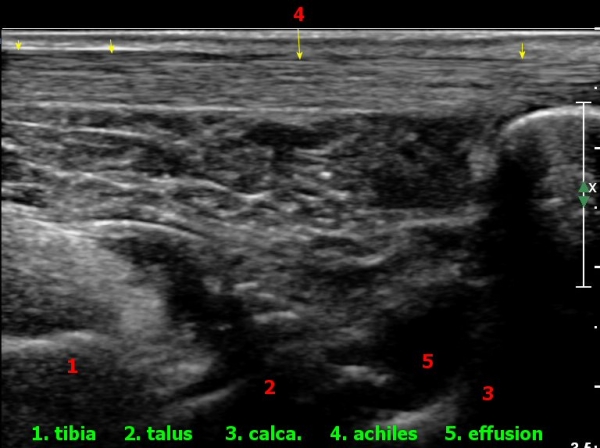

ÃÊÀ½ÆÄ°Ë»ç : ¹ß¸ñ °üÀý Á¾´Ü¸é°Ë»ç¿¡¼­ ¹ß¸ñ °Å°ñ ¿¬°ñÀÌ ¾ã¾îÁ®(thinning) º¸ÀδÙ(»çÁø 1).

,¾ÆÅ³·¹½º°ÇÀ» âÀ¸·Î °üÂûÇÑ ¹ß¸ñ µÚ Á¾´Ü¸é°Ë»ç¿¡¼­ °Å°ñÇϰüÀýÀÇ ¼ö¾×Àú·ù°¡ °üÂûµÈ´Ù(»çÁø 7).